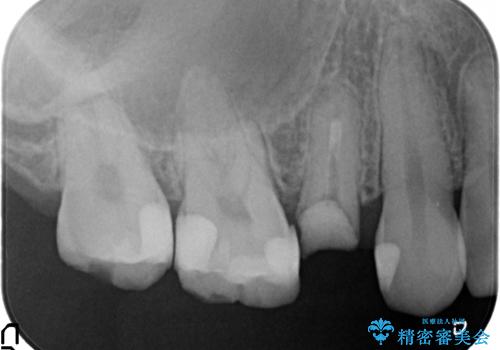

- 他院にて右上5番目の歯の根管治療を行っていたが、痛みが引かないため当院にいらっしゃった方の症例です。

右上5は再根管治療を行い症状の緩解を確認後、オールセラミッククラウンによる補綴を行いました。

右上6、7番目の歯もしみるとのことだったので古い樹脂及び虫歯を除去後、オールセラミッククラウンによる補綴を行いました。

※右上5は歯肉縁下まで虫歯だったため歯冠長延長術を提案しましたが、希望されませんでした。